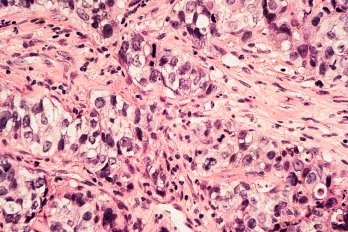

I Lived under the Shadow of My Dad’s Cancer. Then the Same Cancer Came for Me

We are vulnerable creatures no matter how much time we spend telling ourselves otherwise

For half a century, we have thrown everything we have at the disease, but we are no closer to curing it